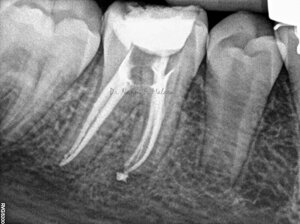

Controllo della guarigione a 7 mesi dalla terapia endodontica (Alla radiografia si nota come le lesioni ossee siano guarite, e la densità della trabecolatura ossea sia tornata alla normalità)